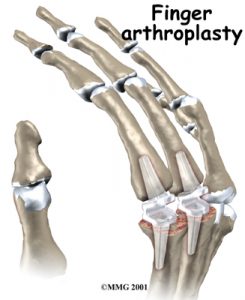

2 – Nos casos de atingimento ósseo moderado ou grave ou luxação articular então optamos pela artroplastia com Proteses de silastic (Figuras 13 a 16)

Estas Proteses maleáveis tem como principal objectivo alinhar o dedo, corrigir a deformidade e aliviar a dor.

No inicio da nossa atividade usávamos Proteses de Swanson, as primeiras a serem descritas.

Posteriormente, mudados para as Próteses Neuflex, cujo desenho e filosofia são diferente, possuindo um pré-formato com 30° de flexão e portanto, menos sujeitas a forças de tensão e compressão durante o movimento dos dedos.

Em 2007 fizemos uma revisão de 124 Próteses, englobando próteses de Swanson e Neuflex. Na nossa experiencia, as próteses Neuflex tem menor taxa de complicações e um maior tempo de sobrevida.

As artroplastias MCF exigem um plano de reabilitação específico e bem conduzido (ver bibliografia).